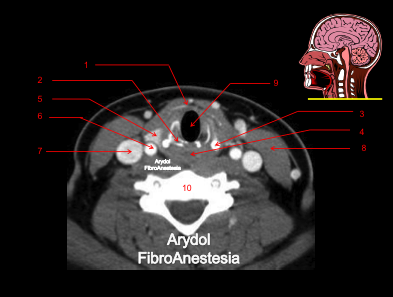

CORTE A NIVEL DE LA SUBGLOTIS Y CARTÍLAGO CRICOIDES

1.Membrana cricotiroidea, 2.arco cricoideo posterior; 3.asta inferior cartílago cricoides; 4.hipofaringe-esófago; 5.glándula tiroides; 6.arteria carótida común; 7.vena yugular interna; 8.músculo esternocleidomastoideo; 9.luz laríngea; 10.vértebra